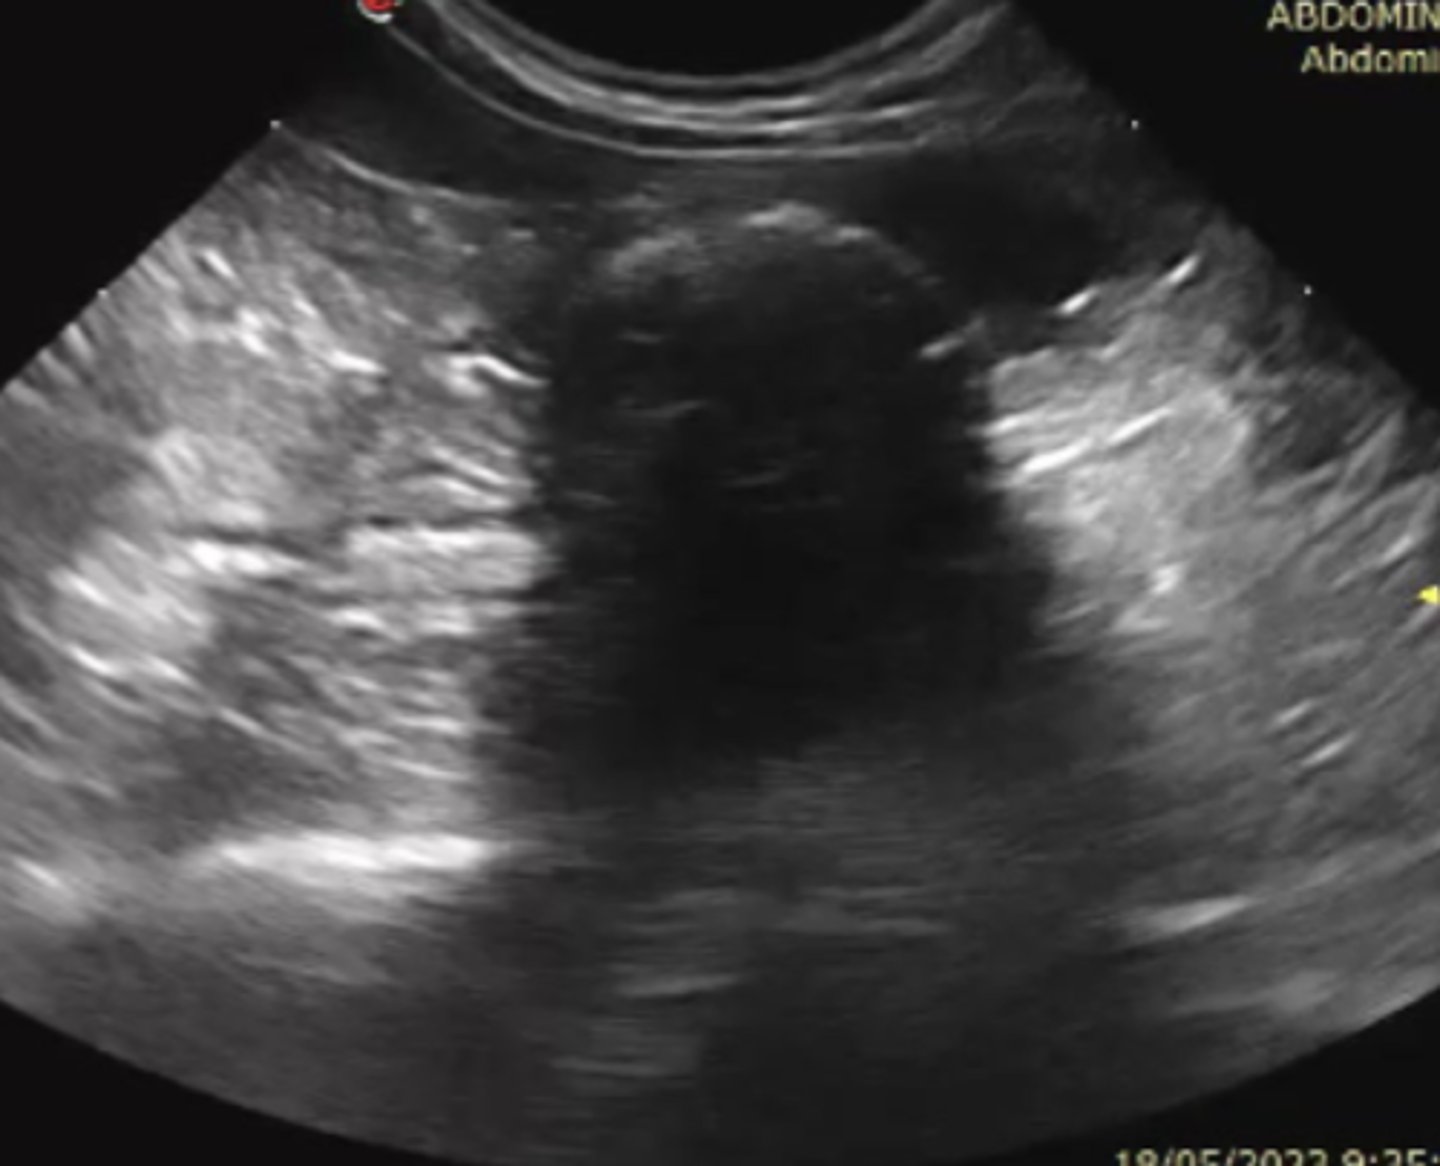

efusión abdominal

patología: